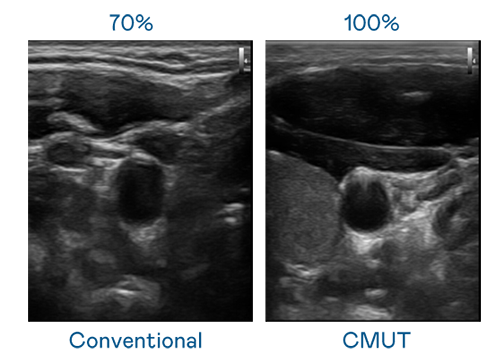

CMUT 技術是一種用電容式微機電元件來產生超音波訊號的技術。與傳統 PZT 壓電式技術相比,CMUT 頻寬增加 30%,更寬頻的超音波訊號讓影像解析度大幅提升,是實現高影像品質醫療超音波掃描、促進精準醫療發展的關鍵技術。

超音波影像的解析度高低,首先取決於探頭能發出的訊號頻寬。伟德国际1946 CMUT 可提供高清晰的超音波訊號,提供高頻寬、高靈敏度、影像紋理細節更高的超音波影像,協助醫護人員縮短影像判讀時間及利用精準的醫療影像進行診斷。